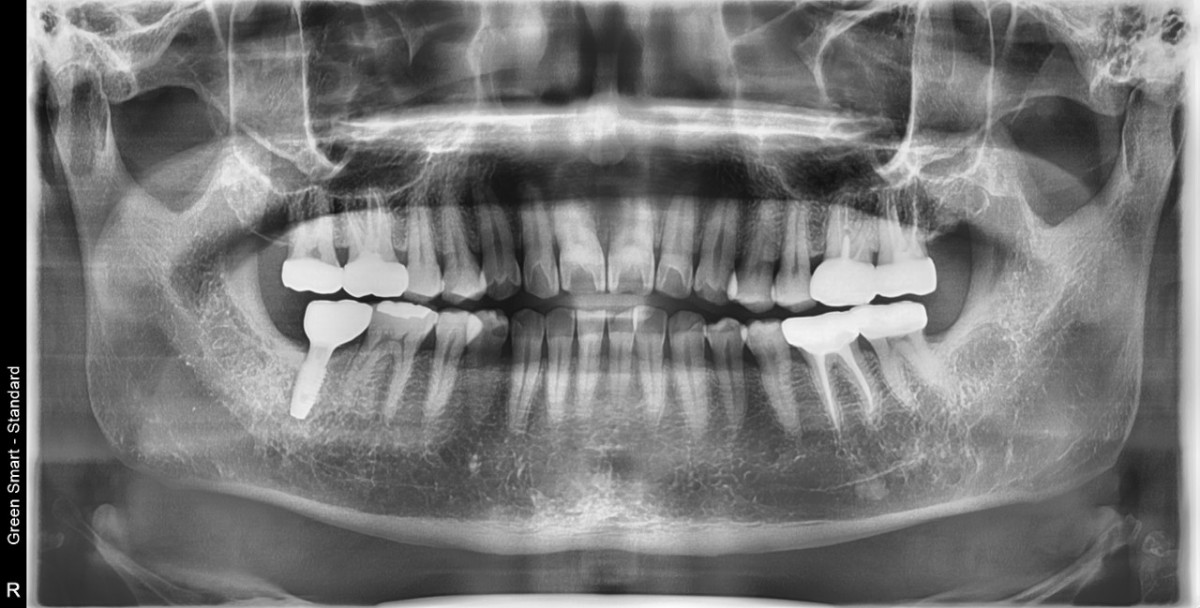

A 47-year-old male patient had a crown with an ill-fitting margin and crack-tooth syndrome in the lower 2nd molar. No systemic issue.

▲torque value after insertion